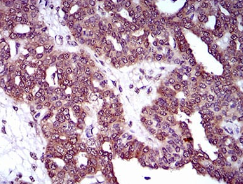

DNM1L Mouse Monoclonal antibody[4E11B]

Immunogen:    Purified recombinant fragment of human DNM1L (AA: 69-213) expressed in E. Coli.

IHC    1/200 - 1/1000